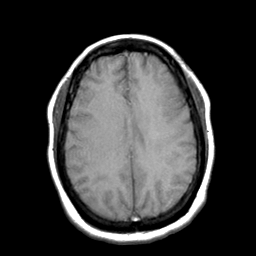

Cerebral hemorrhage, MR Study mr-t1 -- Slice #16

[Home][Help][Clinical] Slice 16